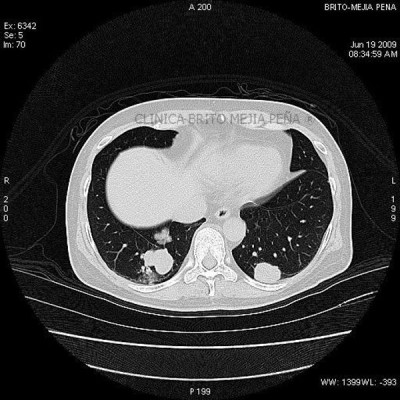

Metástasis pulmonares